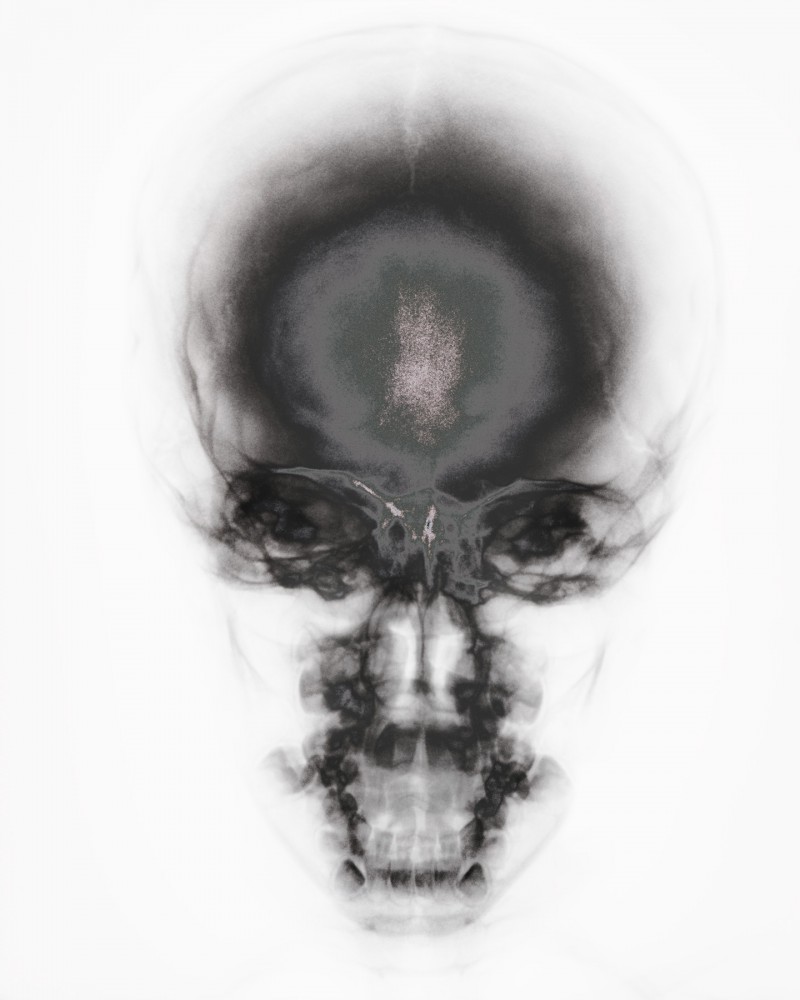

x-rays